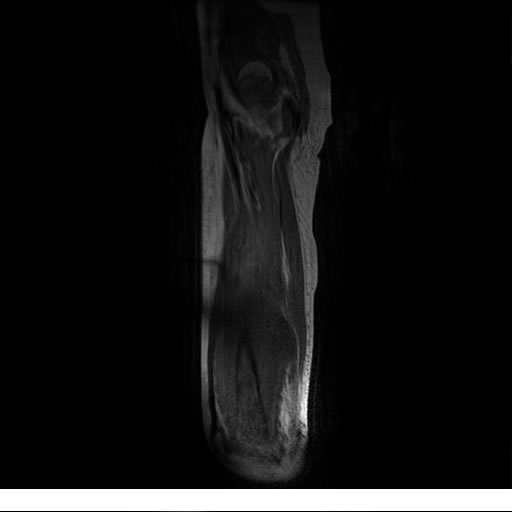

Se realiza estudio de MRI de muslo izquierdo en diferentes planos, con secuencias de Spin Echo, GRE; ponderadas a T1 y a T2, se utilizan pulsos de saturación de grasa y se administra medio de contraste IV a base de Gadolinio en base al peso del paciente.

La diáfisis femoral izquierda muestra reacción perióstica importante, se extiende desde el cuello del fémur, invade trocánteres, diáfisis femoral, medial y distal, es compatible con un proceso infeccioso óseo, el complejo muscular del muslo se ve edematizado.

La resonancia es la modalidad de elección para valorar la extensión intramedular y la infiltración en tejidos blandos, brindando una imagen más detallada del compromiso tumoral. Los hallazgos característicos incluyen:

Lesión de señal heterogénea en secuencias T1 (hipointensa) y T2/STIR (hiperintensa), que refleja necrosis, hemorragia y contenido celular diverso.

Realce intenso y heterogéneo tras la administración de contraste (gadolino), lo que indica vascularización tumoral.

Compromiso de la médula ósea adyacente y de estructuras vecinas, como músculos y neurovasculatura.

Posible presencia de edema óseo y necrosis central.